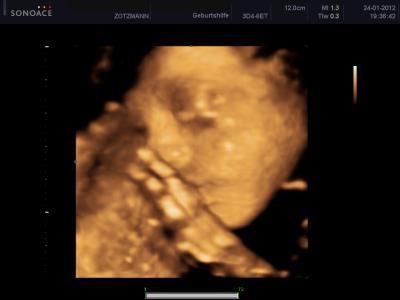

Soooooooooooooooooooo guten Morgen, @Ari 25: Ich habe unter meinem Beitrag von gestern geantwortet, ob die Ex sich noch mal gemeldet hat!!! Die Antwort : Ja! :) Danke an den Rest für eure Antworten, haben mich ein wenig beruhigt, werde wohl zur Apo gehen und mir dieses Planktur20 gegen Haarausfall holen und meine Haare nicht mehr so doll mit heißer Fönluft und tupieren reizen. Und jetzt zu meinem kleinen, persönlichen Star. War gestern ja beim Ultraschall. Die Kleine wiegt genau 1000gr und ist ca. 35cm groß! Ab heute kann ich auch groß 8ter Monat schreiben!!!!! Leider, hatte sie die Hand vor dem Gesicht beim 3D Bild machen und der Arzt meinte, dass sie noch ein wenig zu dünn sei und sich noch was anfuttern muss, damit man bessere Bilder bekommt. Soll in zwei-drei Wochen noch mal hin. Musste das 3D dann auch nicht bezahlen, habe aber trotzdem ein, zwei Bilder mitbekommen und bin verliebt. Ehrlich gesagt, finde ich das schon toll, wenn man sein Schatz sieht und sich selber darin erkennt. Sie hat mein Gesicht, aber Papas schöne Lippen! Kleiner Schmollmund!!! Ich lade es mal hoch! Ich liebe sie sooooooo!!! Happy Mom Jasmin :)

Bild zu Unser Engelchen - Forum für April - Mamis